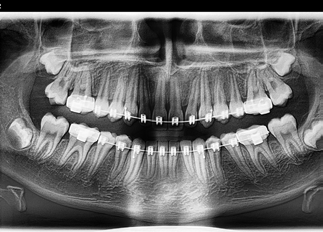

Das PaX-i Plus AI ist ein modernes digitales Panorama-Röntgensystem (OPG), das innovative Bildgebung mit künstlicher Intelligenz verbindet. Es wurde entwickelt, um Diagnosen zu präzisieren, Arbeitsabläufe zu optimieren und die Patientenversorgung nachhaltig zu verbessern.

Dank leistungsstarkem CMOS-Sensor, intelligenter Bildoptimierung und automatisierten Funktionen liefert das System zuverlässig hochwertige Aufnahmen – auch unter anspruchsvollen Bedingungen. Die modulare Bauweise sowie die einfache Integration in bestehende Praxissoftware machen das PaX-i Plus AI zu einer zukunftssicheren Lösung für Zahnarztpraxen und Kieferorthopäden.

CMOS CSI Sensor (5 lp/mm)

ALSA-Technologie

Autofokus-System

- Bildoptimierung durch intelligenten ALSA (Automatic Layer Selection Algorithm)

- Hochauflösender CMOS CSI Sensor (Auflösung 5 lp /mm)

- Autofocus-Funktion mit speziellen Aufnahmeprogrammen (TMJ, Sinus)

ALSA kombiniert automatisch mehrere Schichtaufnahmen zu einem optimalen Bild und reduziert so Fehler durch falsche Positionierung.